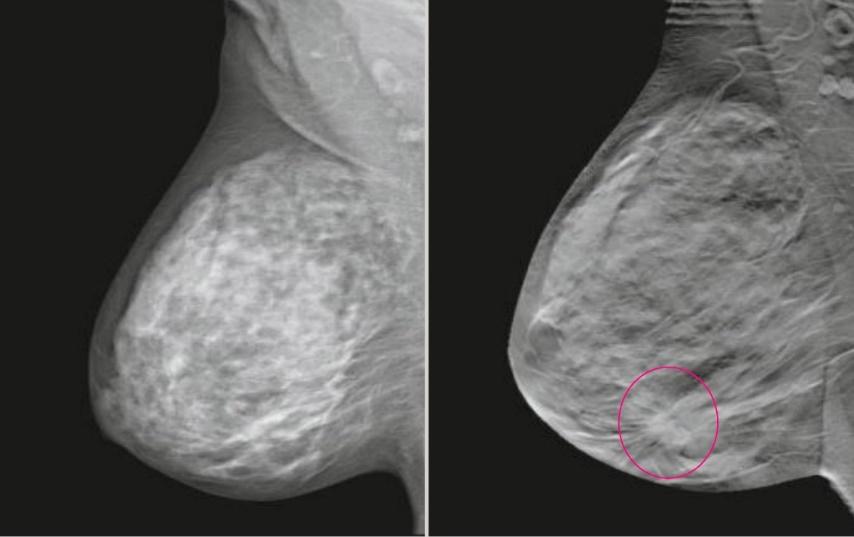

Томосинтез - это реконструктивный рентгенологический метод исследования, представляющий собой последовательность томограмм, произведенных на заданную глубину с фиксированным расстоянием между ними. Цифровой томосинтез (DBT) использует возможности трехмерной маммографии для получения и анализа срезов, что позволяет удалить близлежащие ткани и повысить качество диагностики, особенно при плотной ткани молочной железы.

Пример сравнения классической маммограммы и томосинтезного среза

FFDM (2D) / BTM (3D)

Цифровой томосинтез, или 3D маммография, часто используется вместе с классической 2D маммографией для обследования плотных молочных желез или в качестве дополнительного метода при обнаружении патологий. Основным показанием для выполнения 3D маммографии является высокая плотность молочных желез (ACR C и D). В таких случаях может быть проведена маммография как в 2D, так и в 3D режимах в качестве основного метода обследования для пациентов старше 40 лет. В редких случаях томосинтез может быть использован после маммографии у женщин с низкой плотностью молочных желез для дополнительной диагностики, например, при подозрении на опухоль в молочной железе.

- Повышение визуализации узловых образований на фоне плотной ткани молочной железы.

- Уточнение характера контура узловых образований («звездчатости», «тяжистости»), что дополнительно выявляет от 12 до 45 % патологических находок.

- Уточняет характер ассиметричной перестройки структуры ткани молочной железы.